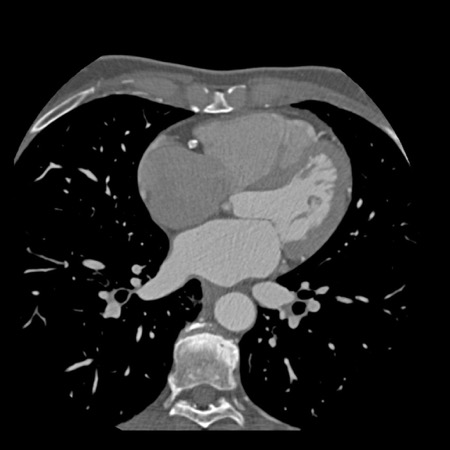

case 1 – CAD-RADS 2/P1

First, scroll through the scan.

Not all images are included. Some images without any abnormalities are skipped

from the series.

How would you describe the findings on the coronary CTA?

The findings are:

- Agatston score of

this patient was 14 (P1). Please, also note the calcification of the aortic valve. - Some partially

calcified and calcified plaques are present in the LAD with mild stenosis

(25-49%). - Calcified-plaque in

the LCX causing minimal stenosis (<25%). - Non-calcified

plaque in the distal RCA causing minimal stenosis (<25%). - This patient classifies

as CAD-RADS 2/P1, which means no further workup is needed.